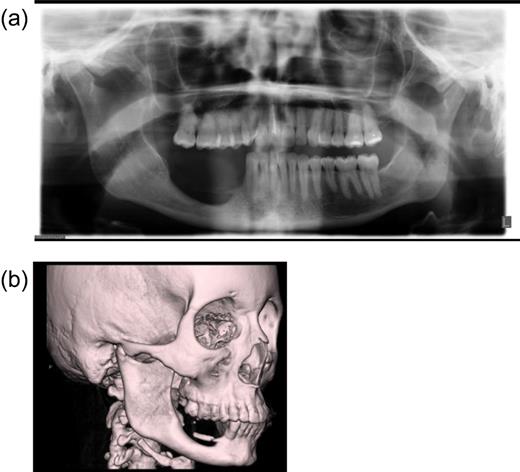

On examination, there is clear absence of teeth on the lower-right side from the canines back (to include the premolar, molar and wisdom teeth) and presence of healthy oral mucosa with laxity to move the submucosa medially. There is a loss of the vertical height of the posterior body of the mandible of about 50% and the vestigial remnants of the lingual plate are just palpable and visible on plain radiograph and CT. Scans show that the superior margin of the resection is well corticated under the inferior dental nerve (Fig. 1a and b). No functional problems exist. As a long-term solution to her defect, the patient wishes to get dental implants. The surgical approach taken, prior to the implants, shall be discussed.

Imaging of the patient's mandibular defect pre-surgically. (a) Radiolocal image of patient's jaw. (b) CT scan of head